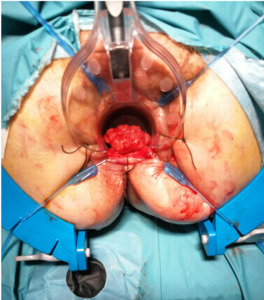

We report the case of a 52-year-old male patient in whom a vegetative lesion of the distal rectum was incidentally identified during urological evaluation for bladder carcinoma. The patient’s medical history was notable for episodes of hematochezia, which had not previously undergone proctological assessment. Endoscopic investigations were conducted (Figure 1); however, biopsy specimens yielded non-diagnostic results. Computed tomography (CT) imaging demonstrated apparent obliteration of the distal rectal lumen by a parietal mass measuring approximately 4 cm. To further characterize the lesion, contrast-enhanced MRI was performed, confirming the presence of an expansive mass in the distal rectum (Figure 2).